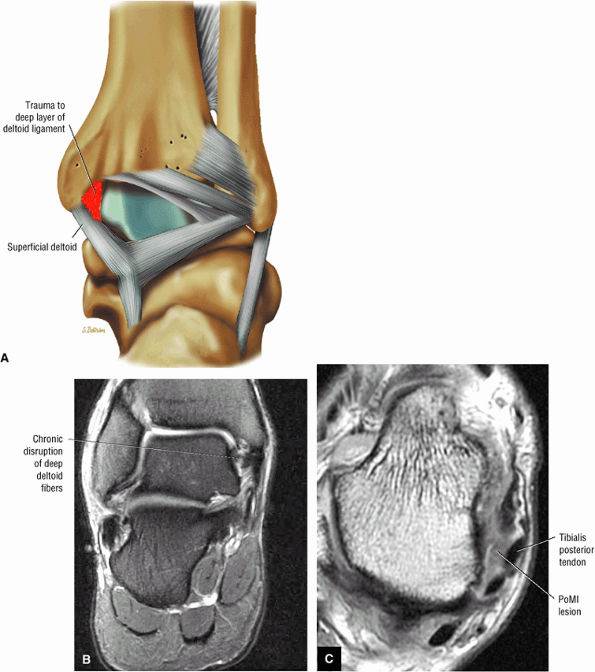

fascicle inserts onto the superior border of the calcaneona vicular ligament. The deep part of the deltoid, which is rectangular, consists of a small anterior component (the anterior tibiotalar ligament) and a strong posterior component (the posterior tibiotalar ligament) (Fig. 5.64). The posterior tibiotalar ligament represents the strongest part of the entire medial ligament complex. The deep portion of the deltoid ligament, covered by synovium, is intra-articular.

![]() |

|

FIGURE 5.58 ● transverse section through the midcalf shows the anterior and lateral compartments and their contents.